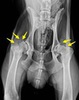

Cadera con artrosis severa. Deformidad de las cabezas femorales , normalmente esféricas, y múltiples osteofitos ( fragmentos óseos ) dañando el fémur y acetábulo ( flechas)

¿QUÉ ES LA ARTROSIS?

La artrosis es una enfermedad articular caracterizada por una degeneración y erosión del cartílago articular, y por la producción de hueso de nueva formación (osteofitos) en los márgenes articulares. Otros sinónimos son “osteoartrosis”, por estar también afectado el hueso subcondral, con esclerosis, inflamación y microfracturas, o “osteoartritis”, para hacer hincapie en la naturaleza ligeramente inflamatoria del proceso, sobre todo a nivel de la membrana